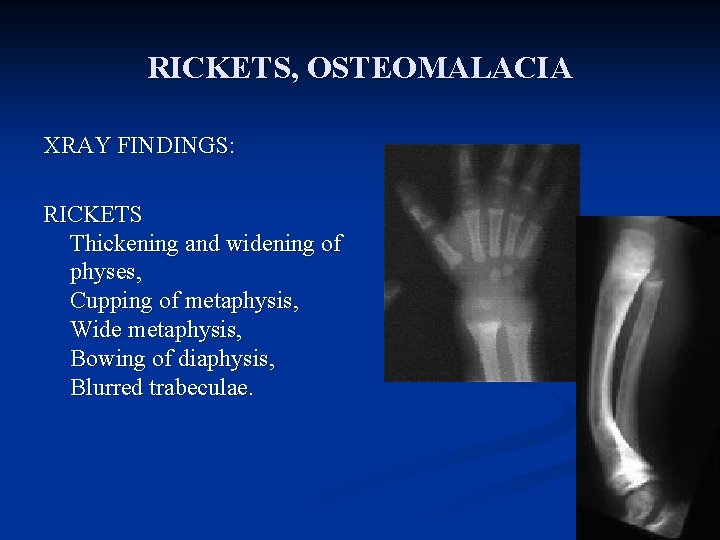

RICKETS, OSTEOMALACIA XRAY FINDINGS: RICKETS Thickening and widening of physes, Cupping of metaphysis, Wide metaphysis, Bowing of diaphysis, Blurred trabeculae.

Radiological findings of rickets n n n Generalized osteopenia Widening of the unmineralised epiphyseal growth plates Fraying of metaphysis of long bones Bowing of legs Pseudo-fractures (also called loozer zone) n n n Transverse radio lucent band, usually perpendicular to bone surface Complete fractures Features of long standing secondary hyperparathyroidism (Osteitis fibrosa cystica) n n Sub-periosteal resorption of phalanges Presence of bony cyst (brown Tumor)